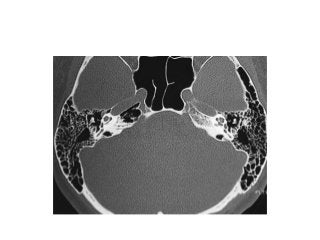

Temporal bone CT. Look at the sub-cochlear canaliculus or sub-cochlear

tunnel that can allow endoscopic transcanal retrocochlear access to the IAC

and drain the petrous apex cells